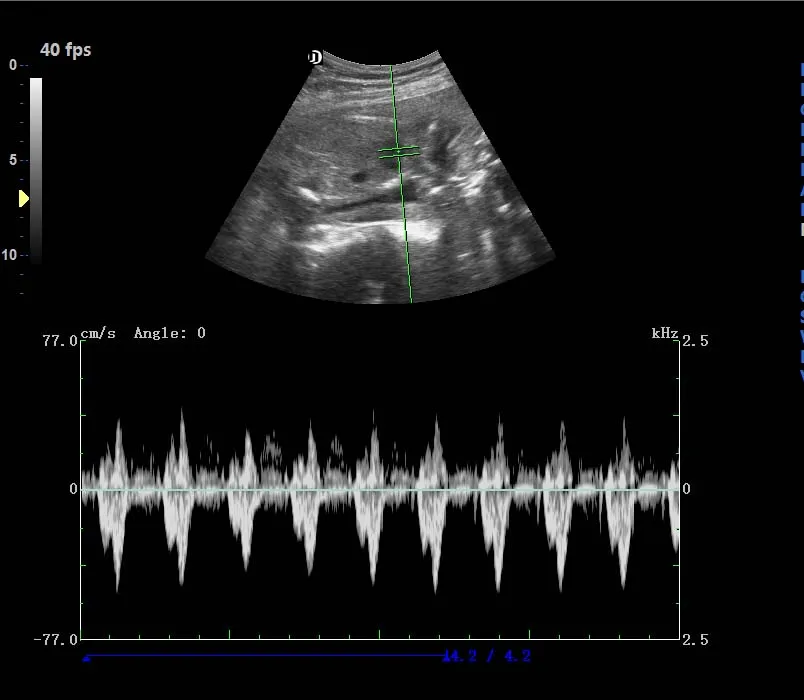

Operating Mode | B, 2B, 4B, B/M, M, B/C/D, B/D, CW, PW, velocity, power(direction), histogram, triples/duplex etc. |

Standard Configuration | Main Unit 3.5Mhz convex probe 4D Volume probe and software 19'LED display with 10.4’ touch screen CW function ( work with phased array probe) USB ports, DICOM 3.0,DVD-RW |

Optional Configuration | 6.5Mhz R10 trans-vaginal probe 7.5Mhz linear probe 2.5Mhz phased array probe Elastography Any Printer |